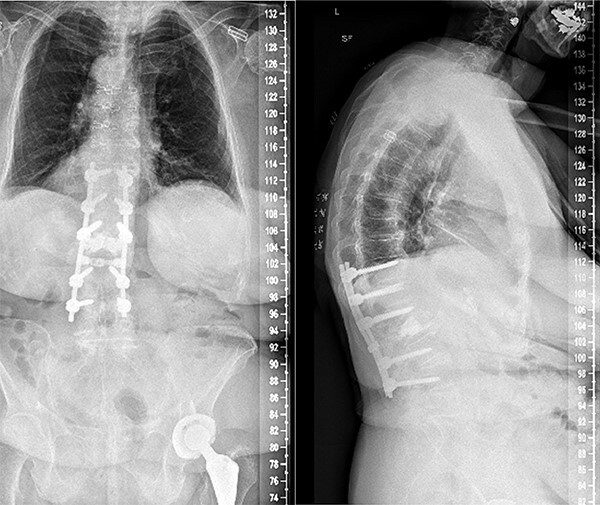

Figure 3.

Anterior–posterior and lateral radiographs of the patient’s spine postoperatively, following L1-L2 laminectomy and T11-L4 posterior fusion.

Segmental spinal instrumentation was placed at L4, L3, L1, T12, and T11 with appropriate positioning of the screws confirmed with biplanar fluoroscopy. Laminectomy was also performed at L2 and L1 with adequate decompression of the neural elements. The fracture was thereafter reduced using gentle cantilever maneuvers. One crosslink was placed, and a final fluoroscopic image confirmed the appropriate positioning of implants and reduction of the fracture and deformity. The wound was copiously irrigated, and the posterolateral spine was decorticated and packed with local autograft as well as demineralized bone matrix. Plastic surgery ensured proper closure using muscle flap reconstruction of the patient’s posterior spine wound. Follow-ups at 2, 4, and 7 weeks later all revealed that the patient no longer had stabbing or throbbing pain, gradual improvement of the back pain down to a 3/10 in severity, well-tolerated ambulation with a walker and assist, normal CNII-VII, 5/5 strength bilaterally upper and lower extremities, and mild back soreness. Postoperative follow-up at 2 years still revealed no complications associated with the procedure with the patient having minimal back pain and soreness, supported by lateral and axial radiographs (Fig. 3).